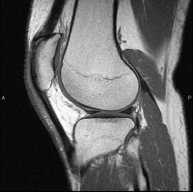

Exploració ideal per estudiar les lesions en músculs isquiotibials i quàdriceps, sovint lesionats en esportistes. També permet una bona valoració de tendons i de nervis perifèrics. La durada aproximada és de 20 minuts. No utilitza radiació ionitzan. - RM de Genoll

Exploració per estudiar lesions a l'articulació, com trencaments dels meniscals i dels lligaments creuats (únicament es poden detectar amb aquesta prova), condropatia o desgast del cartílag i moltes altres alteracions derivades de l'activitat esportiva i dels canvis degeneratius (osteoartrosi). La durada aproximada és de 18 minuts. No utilitza radiació ionitzant. - RM de Cama